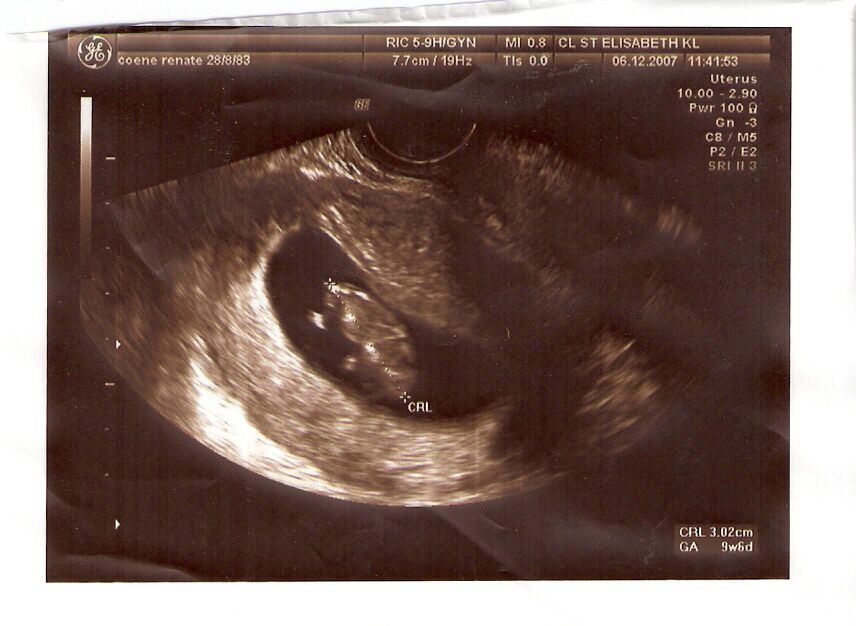

In het ziekenhuis aangekomen (spoed) controleren ze mama haar bloeddruk. Deze blijkt in orde te zijn en ze sturen mama naar de afdeling gynaecologie. Daar aangekomen is mama haar dokter net bezig met 2 bevallingen te begeleiden. Mama moet een hele lange tijd wachten en uiteindelijk komt er een assistent-gynaecoloog mama halen voor een echo. Weer wordt er een inwendige echo gedaan. Dan ziet mama mij terug! Ik ben al een heel stuk gegroeid (al 3.02 cm) en ben tiptop in orde. De gynaecoloog weet niet waarvan de bloeding komt en besluit dat mama enkele dagen moet rusten.

Mama en papa zijn heel opgelucht dat ik ok ben. Mama heeft in het ziekenhuis weer enkele fototjes van mij gekregen die je hier kan bewonderen.